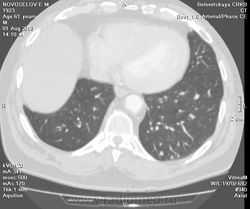

Мужчина оперирован по поводу BL щитовидной железы.Неоднократно проходил КТ в других лечебных учреждениях, у нас- впервые.Ставились заключения:MTS в лёгкие и лимф.узлы средостения слева.Образование слева увеличилось.Жалуется на одышку, не верит в заключение о MTS,просит узнать мнение других специалистов.

Метастазов в легкие не вижу. Похоже на лимфоузел в головке левого корня. Если позволите, запаздываете с началом исследования, плотность контраста в легочных артериях должна быть выше, чем а аорте. А одышка, не мудрено, легочная ткань диффузно уплотнена по типу "матового стекла", написал бы какую-нибудь интестициальную пневмонию, по типу альвеолита, может быть и гиперчуствительный пневмонит (не разберу есть или нет внутридольковые очажки), посмотреть бы изначально легочное окно, а не восстановленное из мягкотканного.

В диф. ряд: саркоидоз, атипичная форма.

Кажется,я понял,что Вы имели ввиду.Очажки стрелочкой указал.Согласен с тем,что очаги на фоне отображеничя сосудов кажутся фантазией,но они присутствуют.

Коллега, вынужден извинться и дезавуировать свой первый пост. Пересмотрел. Да, есть очаги, и они - вероятнее всего, метастазы.

Единственное,что напрягает,так это то,что эти изменения у пациента более 1,5 лет.А вид внешний у него не так уж и плох.А слева это всё-таки лимфоузел, а не периферическое образование в S3?

Думаю, да. Слишком близко лежит к легочной артерии.